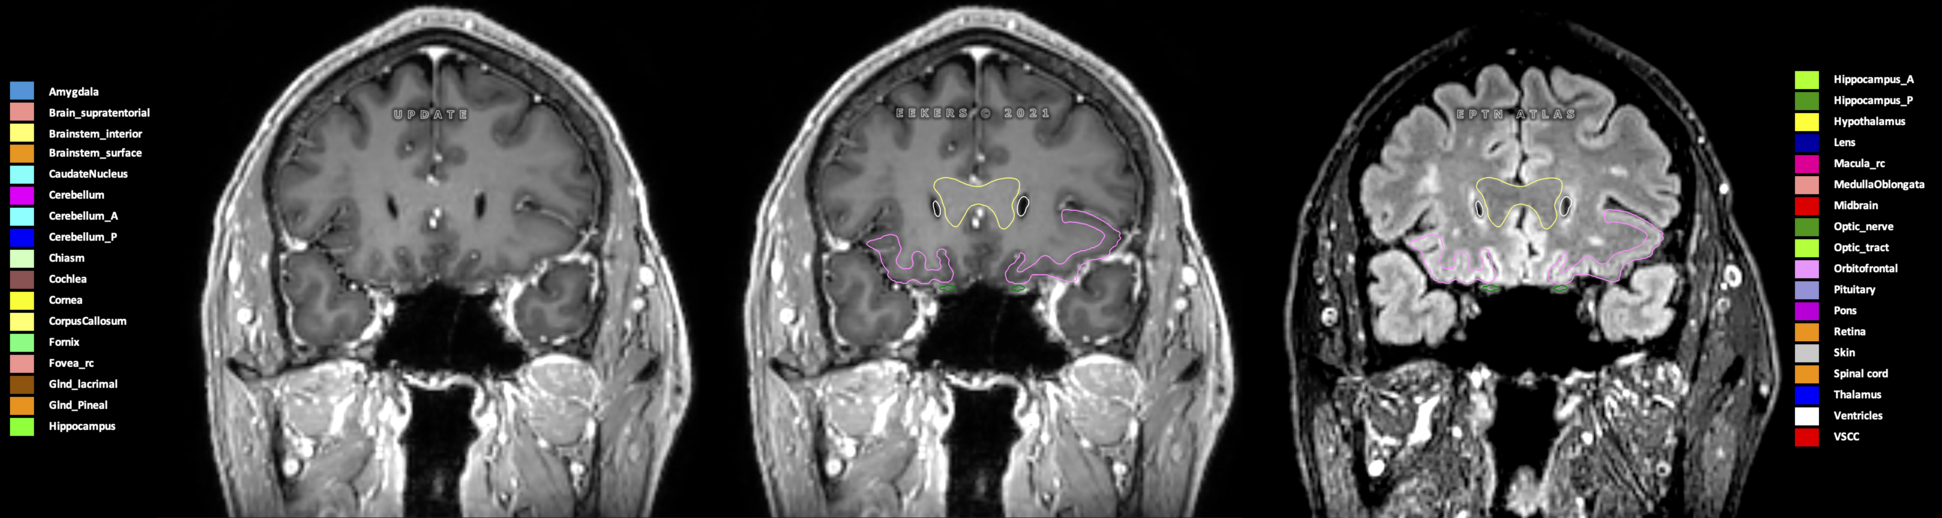

Eekers et al. have published an international neurological atlas for contouring of organs at risk in consensus with the European Particle Therapy Network (EPTN) in 2018 and an update in 2021. The purpose of this consensus atlas is to decrease inter- and intra-observer variability in delineating OARs relevant for neuro-oncology.

Included are all OARs known to be relevant for radiation-induced toxicity in neuro-oncology: brain, brainstem (midbrain, pons, medulla oblongata), chiasm, cerebellum (anterior & posterior), cochlea, cornea, hippocampus (anterior & posterior), hypothalamus, lens, lacrimal gland, optic nerve, pituitary, skin, and vestibular & semicircular canals. To further facilitate research on cognition, vision and radiological changes after irradiation of the brain, potential clinically-relevant OARs are included: amygdala, caudate nucleus, cerebellum (anterior & posterior), corpus callosum, fornix, macula, optic tract, orbitofrontal cortex, periventricular space (PVS), pineal gland, and thalamus.

Three-dimensional delineation of the 25 consensus OARs for neuro-oncology are shown on CT (WW/WL 120/40, 3000/600), 3T MR images, (T1Gd, T2FLAIR 1mm) and 7T MR (MP2RAGE 0.7 mm). All are presented in transversal, sagittal and coronal view.